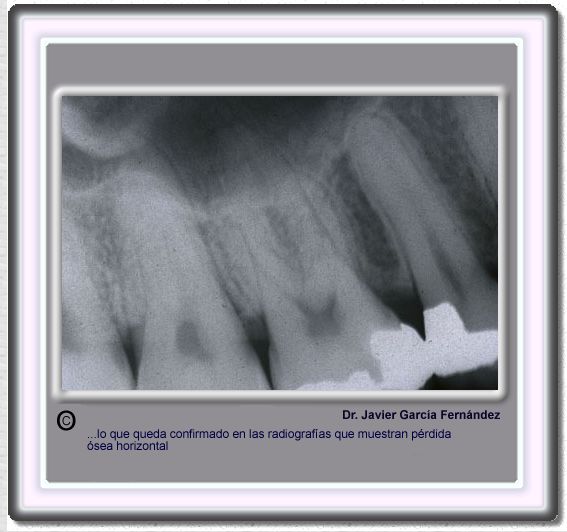

image 510